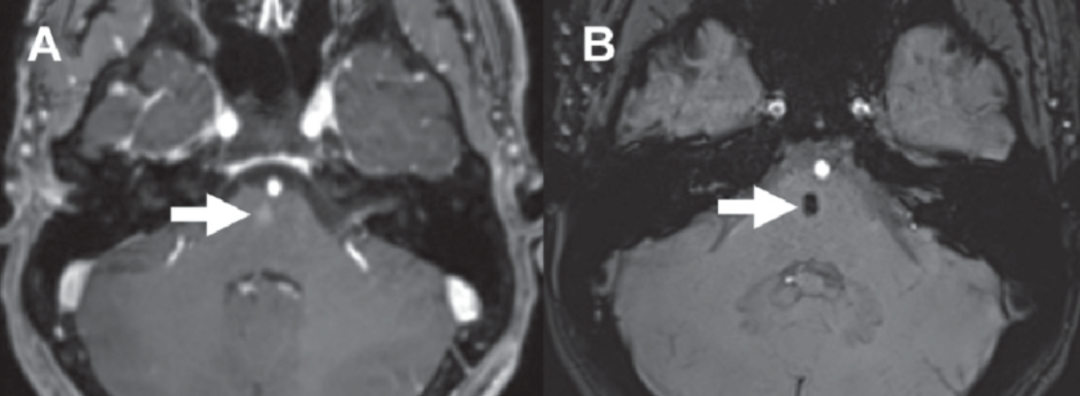

脑干毛细血管扩张症,SWI 低信号,结节样强化,强化程度要小于静脉